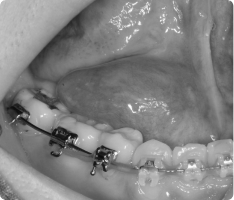

영구치가 나와야 할 시기가 지났는데 잇몸 속에 묻혀 나오지 못하는 치아가 있습니다.

이를 ‘매복치’라고 하며, 흔히 송곳니(견치)에서 많이 발생합니다.

치아가 스스로 나오지 못하면, 교정치료와 함께 개창술을 통해 치아를 밖으로 끌어내야 합니다.

- 국소마취 후, 치아가 묻혀 있는 잇몸을 작게 열어 치아 머리(치관)를 노출시킵니다.

- 치아 표면에 교정용 버튼(장치)을 부착하고, 교정력(작은 고무줄·와이어)을 이용해 치아를 이동시킵니다.

- 수술 자체는 짧고 안전하게 진행되며, 이후에는 교정치료와 병행하여 서서히 치아가 배열됩니다.